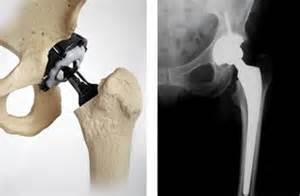

El Tribunal Supremo también hace uso del nuevo Baremo para interpretar el anterior, al igual que han hecho ya diversas audiencias provinciales, estableciendo en este caso la necesidad de indemnizar gastos futuros (prótesis) aun tratándose de un accidentes de circulación de 2009:

«Este criterio ha sido recogido en la Ley 35/2015 de 22 de septiembre, de reforma del sistema para la valoración de los daños y perjuicios causados a las personas en accidentes de circulación, al establecer expresamente en su artículo 115 , el directo resarcimiento al lesionado del importe de las prótesis y órtesis que precise a lo largo de su vida, debiendo la necesidad, periocidad y cuantía de los gastos de las prótesis y órtesis futuras acreditarse mediante el correspondiente informe médico desde la fecha de estabilización de las secuelas, teniéndose en cuenta para su valoración el tipo de secuela, la edad del lesionado, la periodicidad de la renovación de la prótesis y órtesis en función de su vida útil y el coste de las mismas, atendiendo a las necesidades y circunstancias personales del lesionado; gastos que se podrán indemnizar en forma de capital utilizándose el correspondiente factor actuarial de conversión establecido en la tabla técnica de coeficientes de capitalización de prótesis y órtesis incluida en las bases técnicas actuariales a las que hace referencia el art. 48 de la citada Ley».